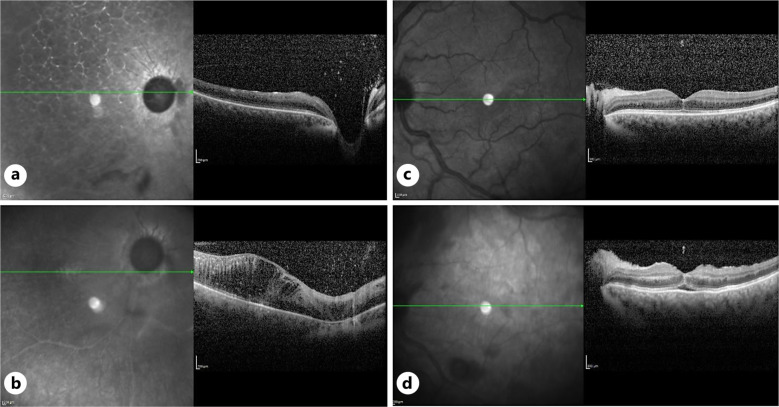

Case presentation: A 28-year-old woman presented to our emergency room with blurred vision in both eyes. She had undergone bilateral cosmetic iris implantation (BrightOcular, Stellar Devices, New York, NY, USA) 6 years earlier in Tunisia. At the first examination, her best corrected visual acuity was hand motion in the right eye and 20/100 in the left eye, and intraocular pressure (IOP) was 45 mm Hg and 30 mm Hg, respectively. Despite the maximum-tolerated glaucoma medical treatment, the elevated IOP persisted, leading to the decision to perform bilateral sequential Baerveldt glaucoma drainage device implantation. However, she subsequently developed combined central retinal artery and vein occlusion in the right eye and hypotensive maculopathy in the left eye; the latter resolving within 1 month. Two months post-surgery, extensive neovascularization above the implant of the right eye was observed, and this was successfully treated with three sequential injections of bevacizumab.

Conclusion: Cosmetic iris implantation is associated with severe, sight-threatening complications. Herein, we describe a previously unreported case of angle neovascularization with new vessels growing over the artificial iris implant. The condition regressed after intravitreal anti-vascular endothelial growth factor injections.